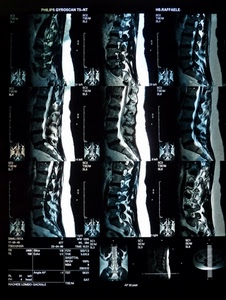

857° Singola Voto: 33.79 |  1057° Colonna vertebrale Voto: 25.82 |